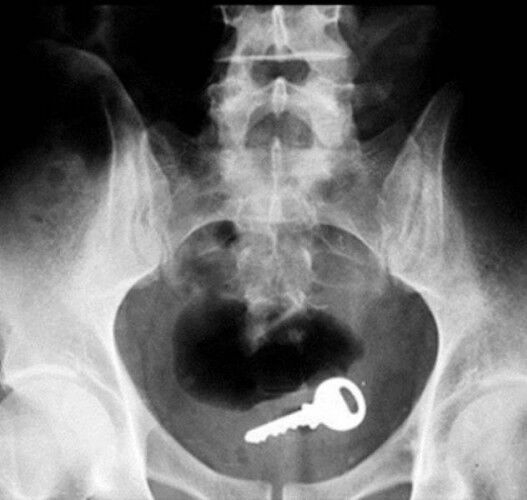

Röntgen Filminde İnsanların İçinden Çıkan Acayip Maddeler

2 / 9